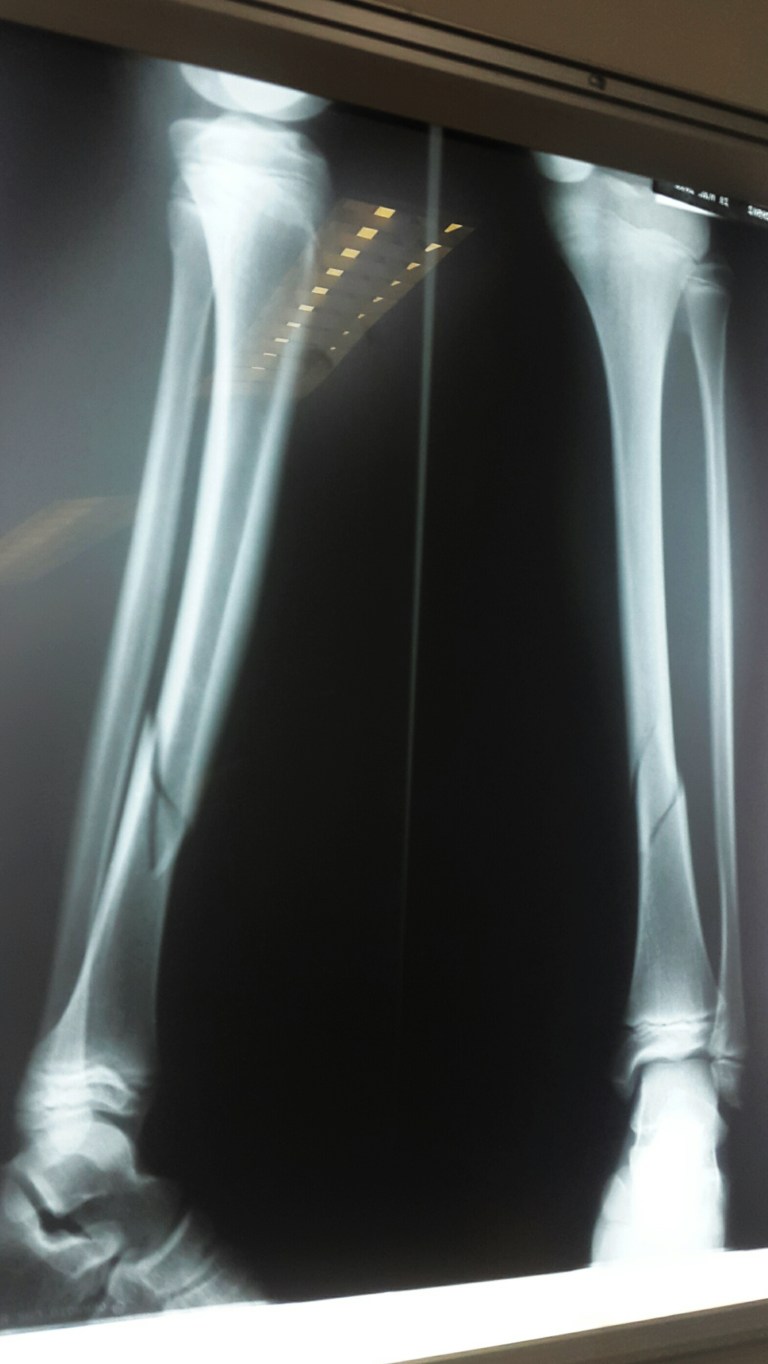

Luca one of the young boys broke his leg playing football so I had to take him off to the hospital to get it all fixed up. A nasty break